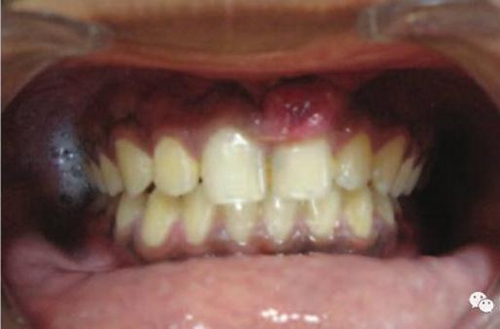

激光治療后即刻

治療前和2個月后效果對比